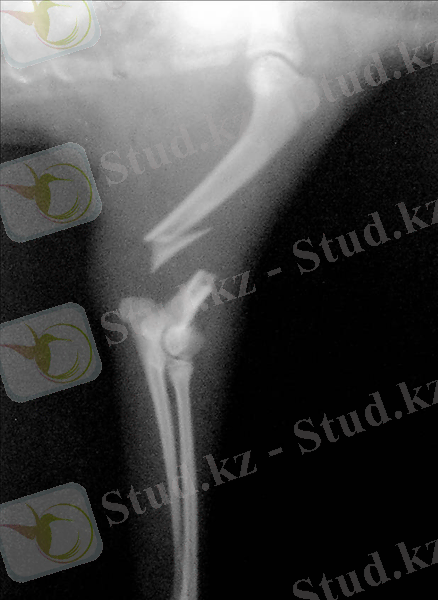

Картинасы:

Ортан жіліктің сынуы

Сиырдың ортан жілігінің сынуы өте көп кездеседі. Сүйек толық сынған жағдайда, сүйектің сынған жақтары бір-бірінен алыстайды. Жартылай сынған жағдайда - жарықтар түседі, шеттері мүжіледі; ашық сынған жағдайда - терісі жыртылады, ал жабық сынғанда - терісі бүтін күйде болады. Сүйектің сынуы буындардың ішінде және буынның сыртындағы сынықтар түрінде кездеседі.